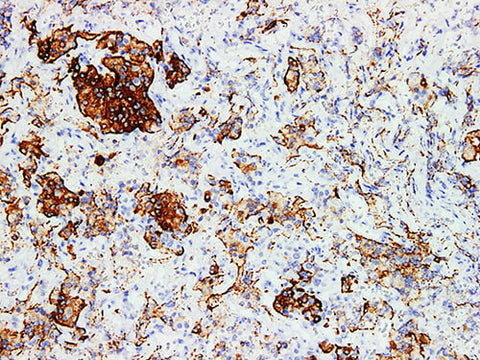

Applications IHC-P

Tissue Specificity Pituitary tumor

Growth hormone(GH) is a hormone synthesized and secreted by growth hormone cells in anterior pituitary, which can promote protein synthesis and bone development. Human Growth Hormone(GH) Monoclonal is mainly used for functional classification of pituitary adenomas.